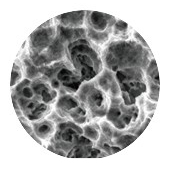

S.L.A. Surface

S.L.A. surface with optimal roughness. Enlarged bone contact area for fast osseointegration.